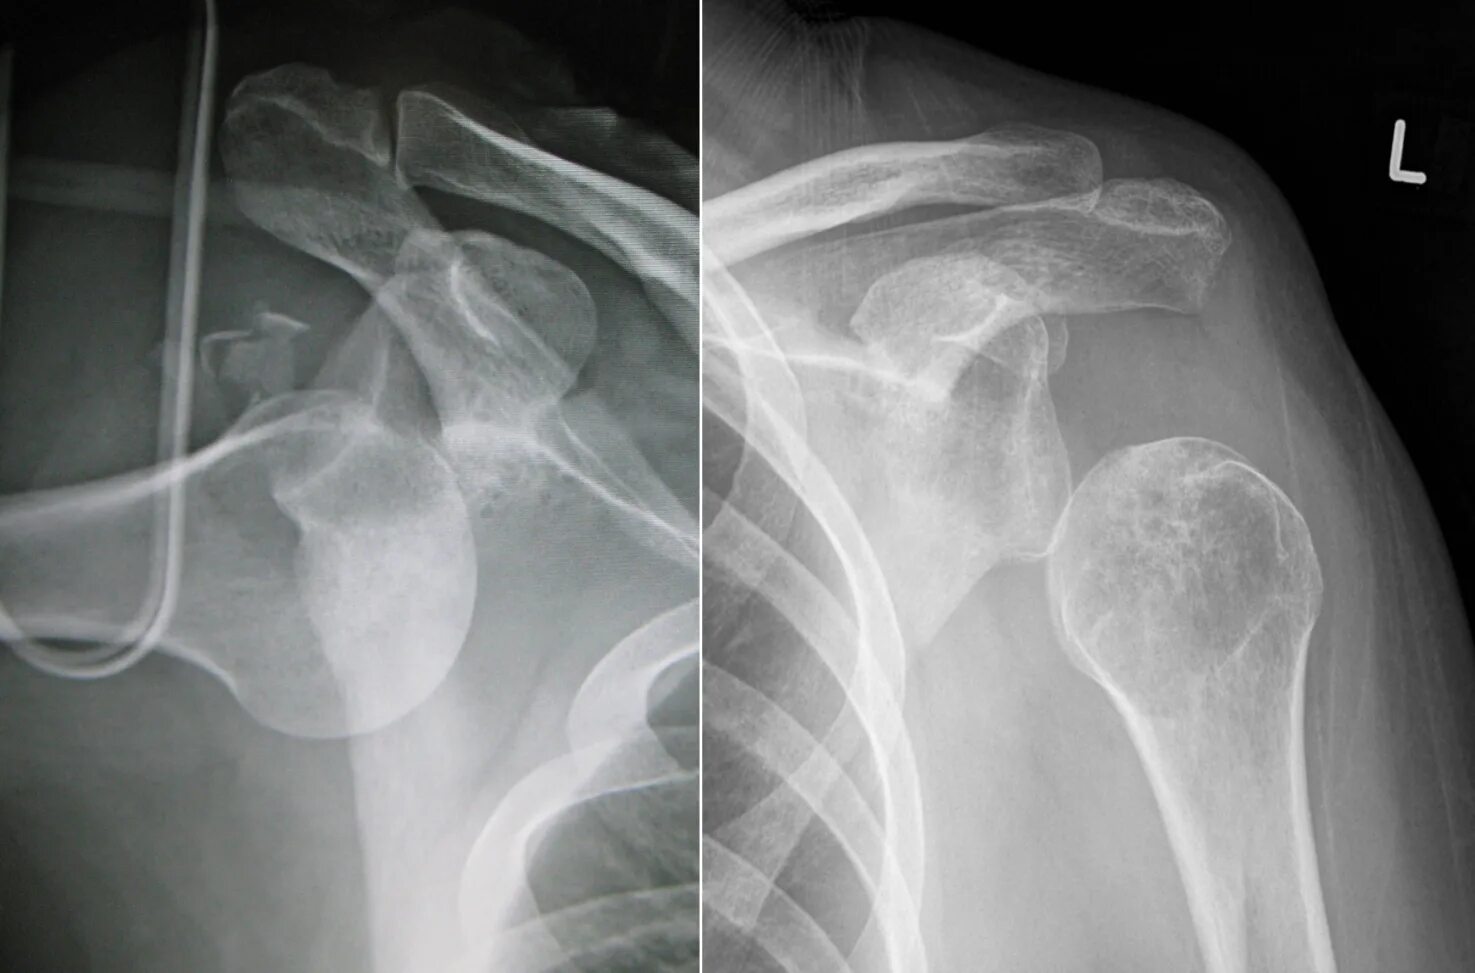

Сколько срастается плечевой перелом